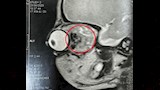

نجح طبيب العيون الدكتور أشرف عبدالسلام في تحقيق معجزة طبية، تُضاف إلى سجل الإنجازات الطبية المصرية بعد أن أجرى جراحة في ظروف دقيقة للغاية اعتُبرت الأولى من نوعها في الشرق الأوسط.

وجاءت الحالة شديدة الندرة حيث تبيّن بعد الفحص أن الورم بدأ في التكوّن أثناء وجود الجنين داخل رحم الأم، وهي حالة لا تُسجَّل إلا في عدد محدود جدًا من الحالات على مستوى العالم.

ومع ظهور أعراض تورم العين فور الولادة، قرر الفريق الطبي برئاسة الدكتور أشرف عبدالسلام التدخل الفوري لتجنب فقدان البصر والعين بالكامل خلال الساعات الأولى من حياة الطفل.

جراحة دقيقة في سباق مع الزمن دخل الفريق غرفة العمليات بقيادة الدكتور أشرف عبدالسلام في سباق مع الوقت لإنقاذ الرضيع، واستغرقت الجراحة عدة ساعات متواصلة من التركيز الشديد والتعامل المجهري مع أنسجة في منتهى الحساسية خلف العين.

واستعان الدكتور عبدالسلام خلال العملية بـ أحدث الميكروسكوبات الجراحية وتقنيات استئصال أورام محجر العين، وتمكن من إزالة الورم بالكامل مع الحفاظ الكامل على العصب البصري، ليُكتب النجاح في واحدة من أدق الجراحات التي شهدها هذا التخصص عالميًا.